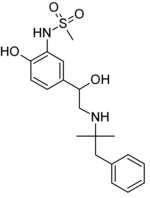

| IUPAC name

N-[5-[2-[(1,1-dimethyl-2-phenylethyl)amino]-1-hydroxyethyl]-2-hydroxyphenyl]methanesulfonamide | |

| C19H26N2O4S | |

| Molar mass | 378.49 g/mol |

Zinterol is a beta-adrenergic agonist.[1]

Its structure is based on soterenol (antiarrhythmic) and phentermine.